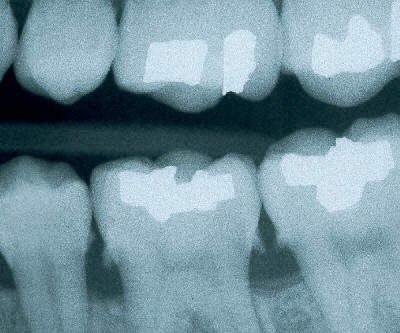

1. What surface require restoration?